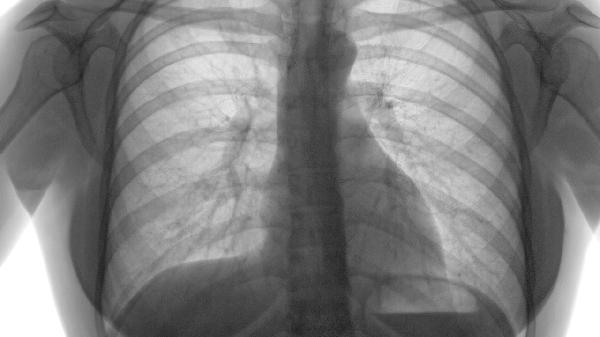

油烟中含有苯并芘、丙烯醛等致癌物。特别是油脂高温裂解产生的多环芳烃,其毒性不亚于烟草烟雾。长期接触可能增加肺癌、鼻咽癌风险。